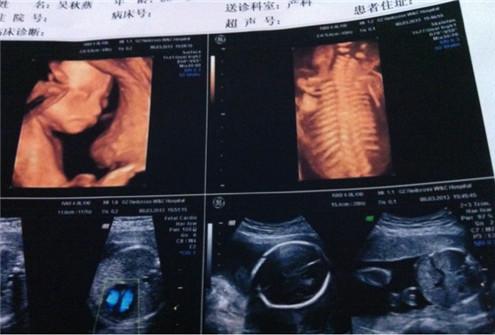

其实啊,在20-28周四维大排畸的时候,医生说不定都有暗示过你哦。

胎儿在4个月的时候就可以检测到性别了,其中男宝宝的性器官比较明显,而女宝宝的性器官并没有那么明显,等胎宝宝到了28周时,准确率就比较高,不同的医生、不同的医院等等,对于鉴定的过程都会导致有误差,在一定程度上都有“反转”的可能。

虽然有时候医生会暗示你一些“宝宝性别的暗语”,也有些医生甚至目无表情很严肃,但不管生男生女只要健康就好。(图片来自于网络)